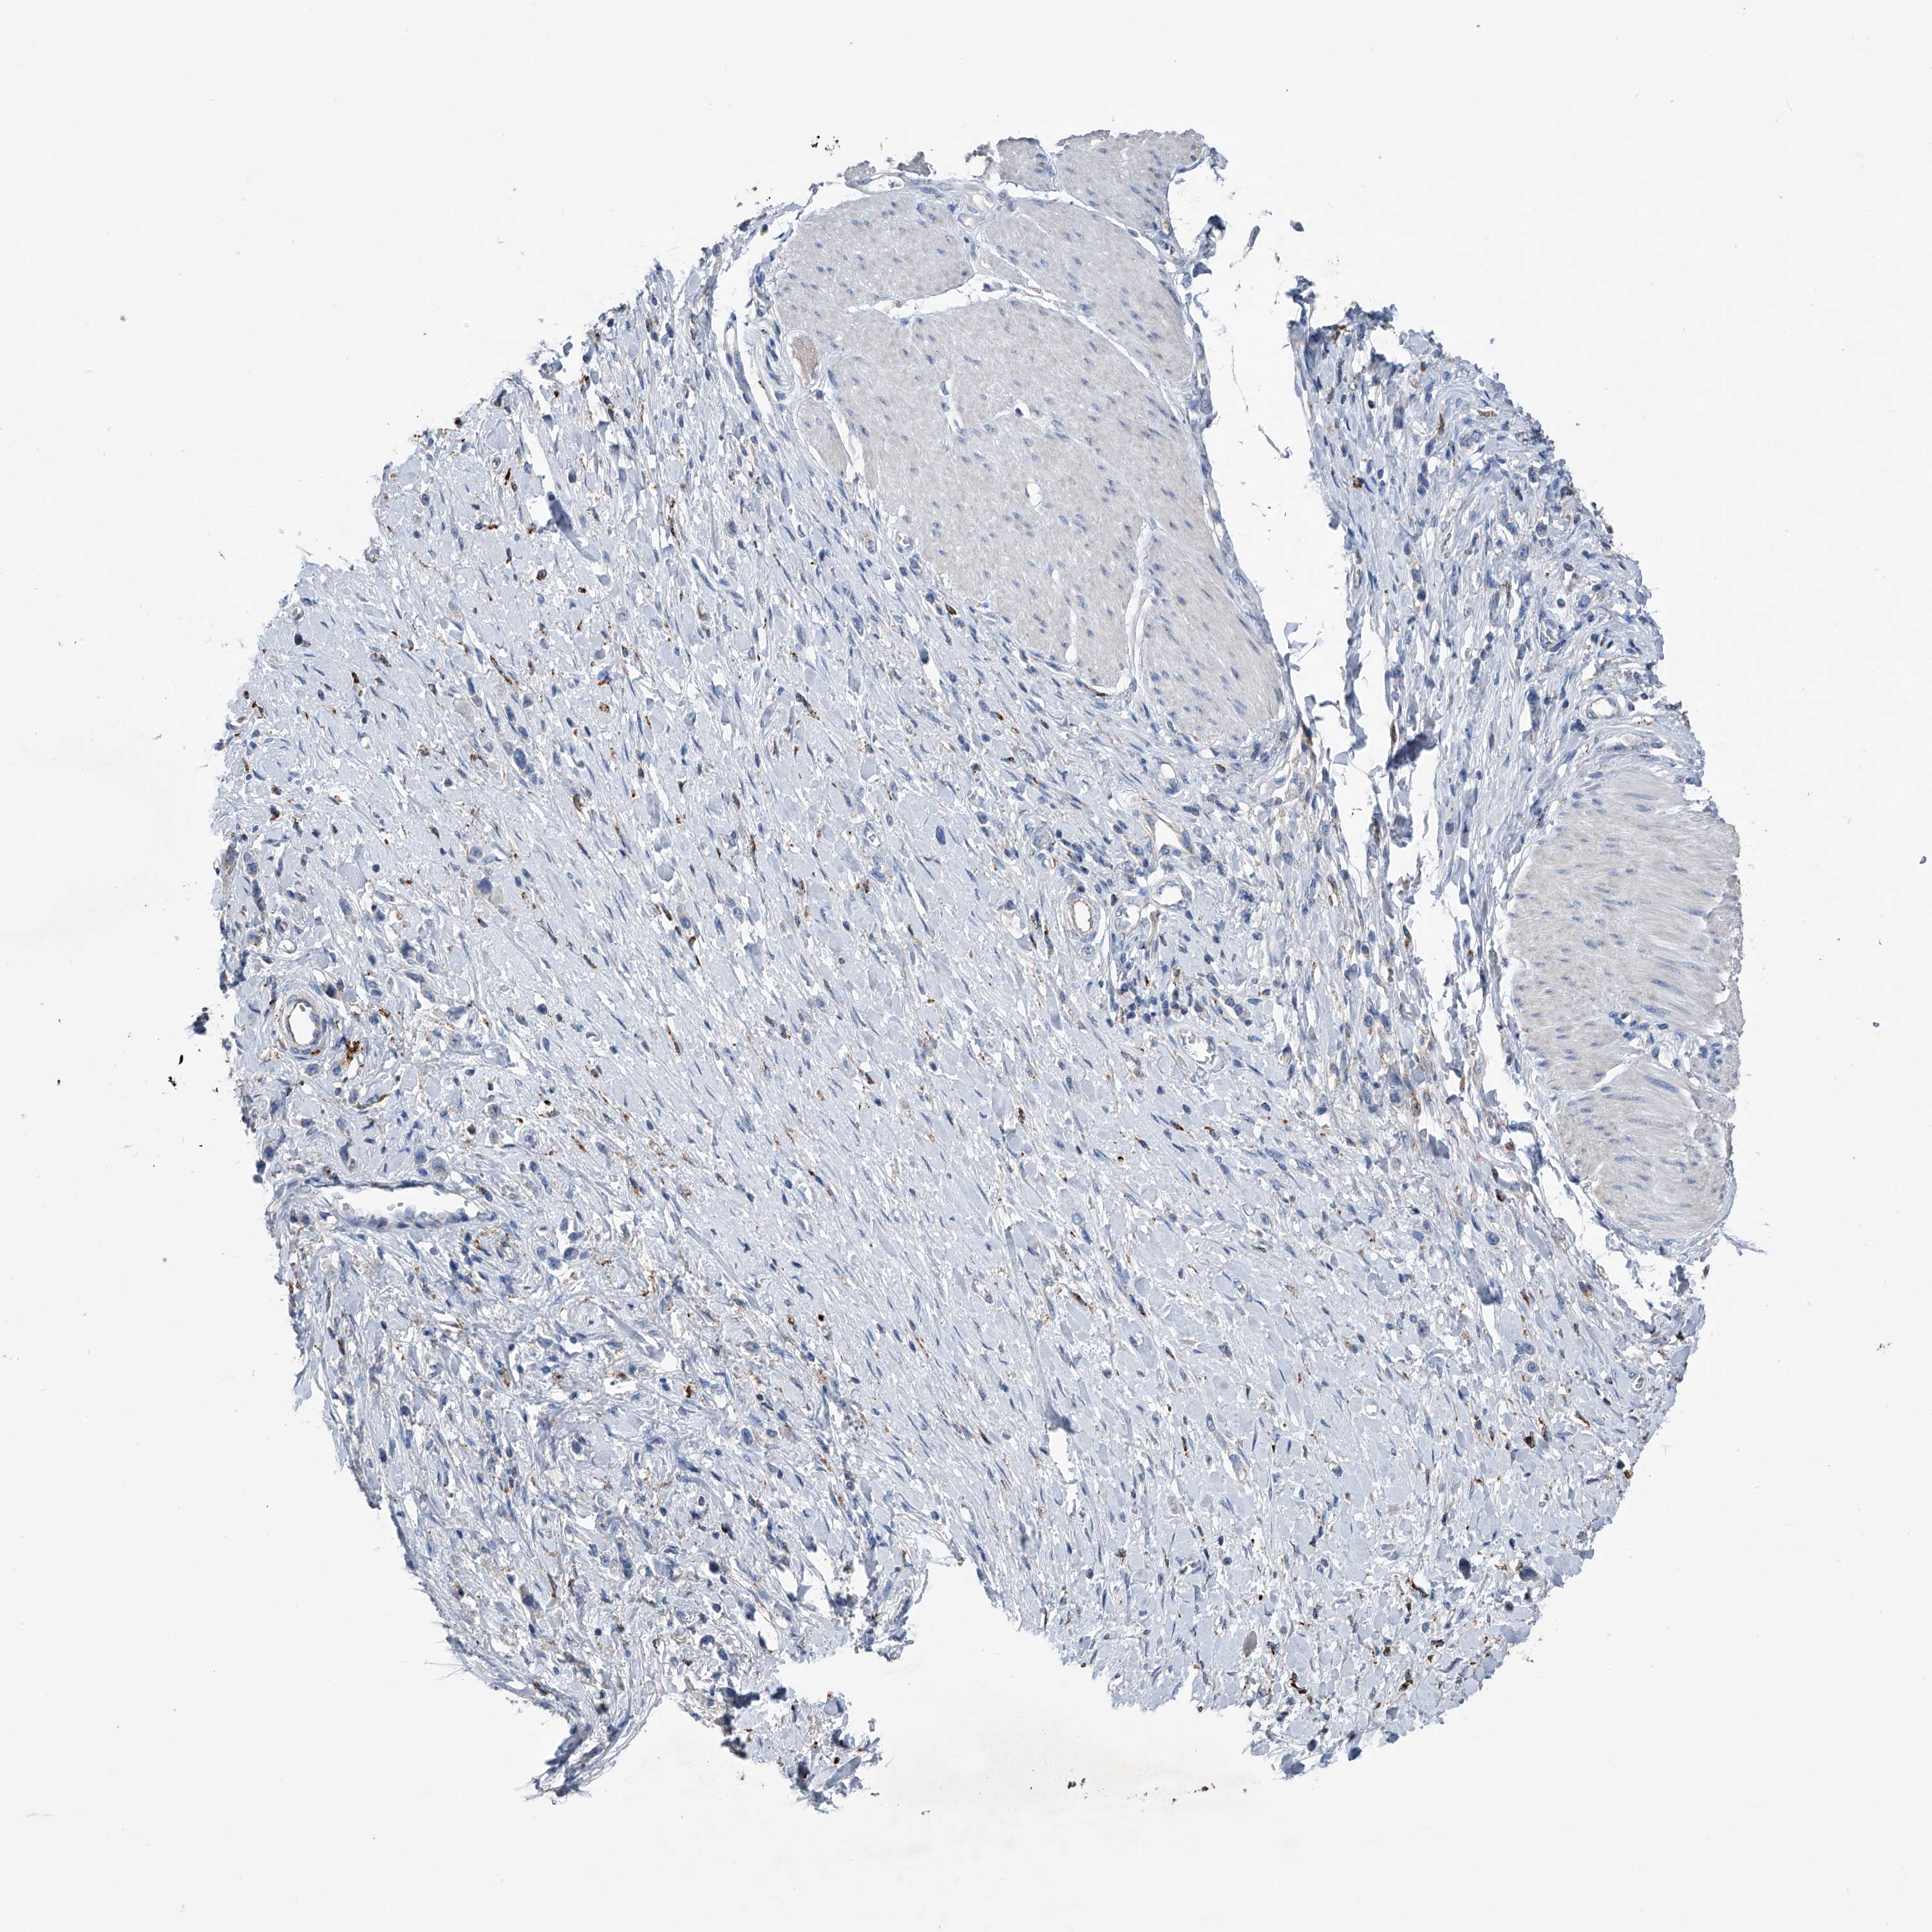

STOMACH CANCER - Protein expressioni

A mouse-over function shows sample information and annotation data. Click on an image to view it in a full screen mode. Samples can be filtered based on level of antibody staining by selecting one or several of the following categories: high, medium, low and not detected. The assay and annotation is described here.

Note that samples used for immunohistochemistry by the Human Protein Atlas do not correspond to samples in the TCGA dataset.

Antibody stainingi

Antibody staining in the annotated cell types in the current human tissue is reported as not detected, low, medium, or high, based on conventional immunohistochemistry profiling in selected tissues. This score is based on the combination of the staining intensity and fraction of stained cells.

Each image is clickable and will lead to virtual microscopy that enables deeper exploration of all samples and also displays staining intensity scores, fraction scores and subcellular localization as well as patient and tissue information for each sample.

Antibody HPA031312

Staining

High

Medium

Low

Not detected

Intensity

Strong

Moderate

Weak

Negative

Quantity

>75%

75%-25%

<25%

None

Location

Nuclear

Cytoplasmic/membranous

Cytoplasmic/membranous,nuclear

Adenocarcinoma, NOS